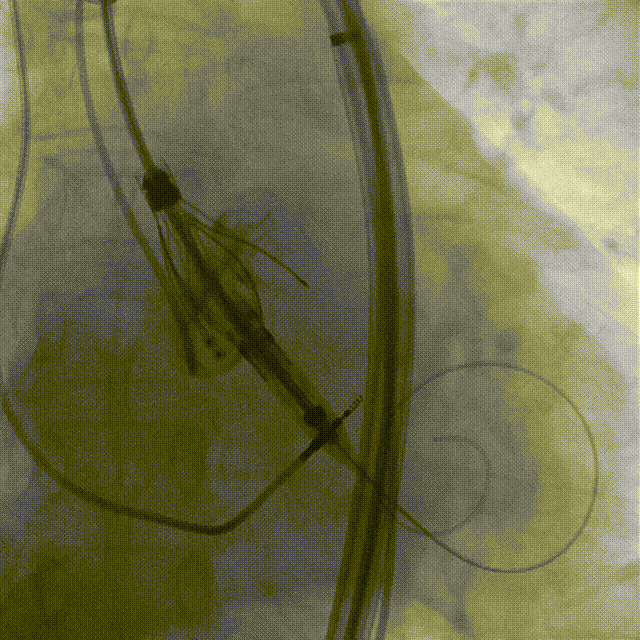

手术过程:5A 标准化流程SOP

术前右窦中心造影

大鞘植入

瓣膜对齐MARK

瓣膜调弯解离

瓣膜锚定键体位确认

瓣膜入窦

左窦确认

深度推进确认

起搏一键释放

术后造影